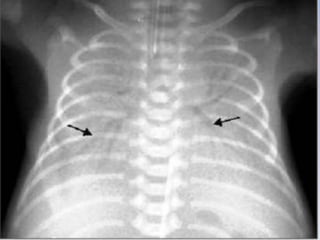

DEEP SULCUS SIGN

• The deep sulcus sign describes the radiolucency extending from the lateral

costophrenic angle to the hypochondrium

• It is an important clue indicating possible pneumothorax in chest x-rays obtained in

the supine position.

• When plain films are taken with the subject in an upright position, the free air in the

pleural space gathers at the apicolateral space.

• In the supine position, the air accumulating at the anterior space forms a triangular

radiolucency that makes the inferior borders of the lateral costophrenic angle

conspicuous

DEEP SULCUS SIGN •The deep sulcus sign describes the radiolucency extending from the lateral costophrenic angle to the hypochondrium • It is an important clue indicating possible pneumothorax in chest x-rays obtained in the supine position. • When plain films are taken with the subject in an upright position, the free air in the pleural space gathers at the apicolateral space. • In the supine position, the air accumulating at the anterior space forms a triangular radiolucency that makes the inferior borders of the lateral costophrenic angle conspicuous